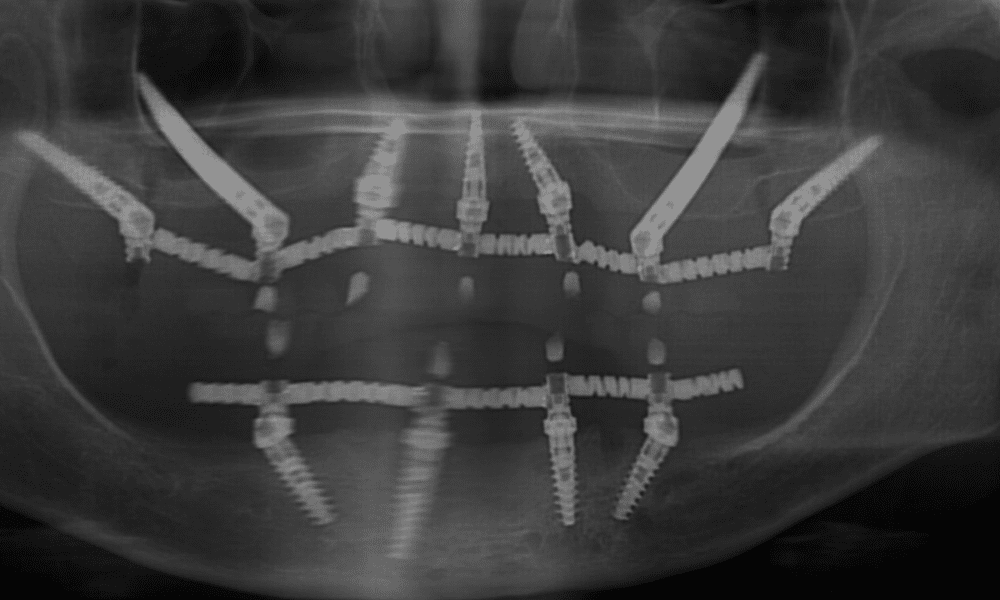

שתלים קצרים הם אחד הפתרונות לבעיה של מחסור עצם בלסת שהיוותה במשך שנים בעיה רצינית עבור מטופלים, שמעוניינים לעבור השתלת שיניים. אבל עם התפתחות הטכנולוגיה הרפואית החלו להיווצר פתרונות לעקיפת הבעיה במקום להתמודד עמה ישירות ראש בראש. אחד הפתרונות הללו, שהולך וצובר פופולריות רבה בזמן האחרון, הוא השתלת שיניים באמצעות שתלים קצרים.

לפני שניגש להסבר על השתלים עצמם, חשוב להבין מדוע עצם הלסת כה חשובה לביצוע השתלת שיניים מוצלחת. כדי שהשתלים יהיו יציבים ויעמדו בפני העומס שיופעל עליהם בפעילות שגרתית כמו צחצוח שיניים ולעיסת מזון, יש לקבע אותם עמוק ככל הניתן בעצם הלסת. הבעיה היא שבאזורים בהם השיניים נעדרות, הגוף חושב שעצם הלסת סיימה את תפקידה ומפרק אותה כדי להשתמש במשאבים הללו במקומות אחרים. כתוצאה מכך, עצם הלסת מתכווצת לממדים בהם קשה לבצע השתלה באמצעים הרגילים. אבל שתלים פחות ארוכים מאפשרים לבצע את השתלת השיניים תחת המגבלות הקיימות בשטח.

שתלים אלו מהווים שתלים דנטליים לכל דבר ועניין, אבל אורכם קצר יותר מאורכם של השתלים הרגילים: למעשה הם דורשים עומק עצם לסת של 5 מילימטרים בלבד, בעוד שמהרגילים נדרש לפחות כפול מכך כדרישת מינימום.

כאמור, עומק השתל משפיע על יציבותו לאורך זמן. כדי לחפות על אורכם המינימלי, האורך הקצר של השתלים הדנטליים מפצה על כך ברוחבם: שטח הפנים ומסת המתכת של השתל גדולים יותר, מה שמעניק לו את היציבות הנדרשת ואחיזה טובה בעצם הלסת הקיימת. קוטר השתל משתנה בהתאם לסוג השן המושתלת (שיניים קדמיות, אחוריות, טוחנות) ועובי עצם הלסת. באמצעות המשוואה החדשה שנוצרה, היציבות שלהם היא שוות ערך לזו של השתלים הארוכים.

הם מהווים פתרון מעולה עבור מטופלים שרוצים לעבור השתלת שיניים אך סובלים ממחסור של עצם בלסת, מאחר והם חוסכים מהם לעבור הליכים של הרמת סינוס ובניית עצם מחדש. השימוש בהם אינו מחייב הליכים של בניית עצם לפני שניגשים להשתלה עצמה, התהליך כולו פשוט וקצר יותר לעומת השתלת שיניים סטנדרטית.